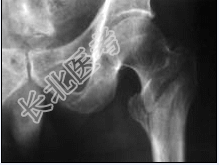

- 多项选择题2.该患者的诊断为: 提示: 该患者 X线如图:

A、右股骨颈骨折

B、右股骨粗隆间骨折